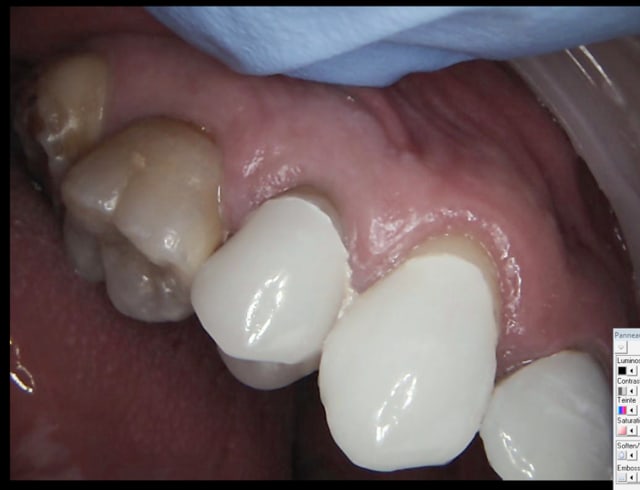

J'avais du les passer déjà quelque part ici. Travail fait en une journée sur 10 dents. J'ai perdu la photo avec écarteur du travail fini, mais cela tombe bien car j'avais pas un très bon maquillage des collets. Ceci dit, patiente AVC avec sourire comme tu vois.

Ou encore fait dans la matinée

Ps: pas de soucis d'occlusion, juste une propulsion pendant la photo finale. Elle avait dû tenter de retrouver machinalement ce contact bout à bout.